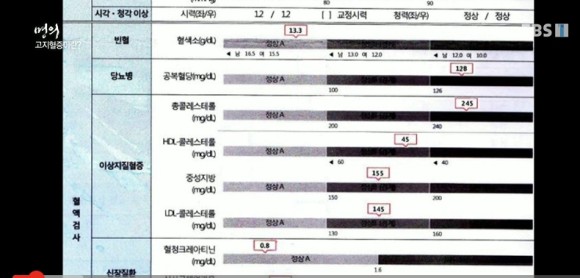

Q. 고지혈은 정말 혈액에 지방이 많은가요?한기훈 심장내과 전문의 응답(서울아산병원) 네, 14시간 정도 금식 후 혈액검사 시 콜레스테롤과 중성지방 수치가 높은 경우를 말합니다.

HDL: 좋은 콜레스테롤 수치가 높아야 합니다.LDL: 동맥경화를 일으킨 나쁜 콜레스테롤, 수치가 낮을수록 좋습니다.고지혈증은 LDL과 중성지방 수치가 높은 경우를 말합니다.

진단 기준 총 콜레스테롤은 200 이하이고 LDL은 130 이하, HDL은 60 이상이어야 합니다.

LDL이 190 넘으면? 유전적 요인에 의한 고지혈증일 수 있으며 고혈압, 당뇨병, 흡연하지 않아도 심장병 위험이 높은 상태로 간주합니다.

환자사례 4 마른 체형의 고지혈증 남자, 총콜레스테롤 291, LDL 196